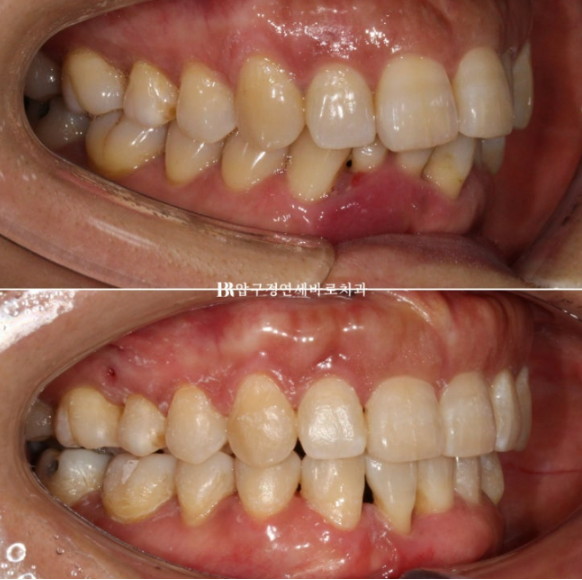

2022.11~24.05

파란 화살표 앞니 자리에 와 있는 송곳니입니다.

앞니쪽 치주염은 꾸준히 관리로 잘 치료가 되었고 앞니 뻗침은 개선이 되었습니다.

윗니 끝단과 아랫입술이 이루는 스마일라인은 중요합니다.

돌출입 해소가 되며 깔끔한 인상이 되었습니다.

치주염으로 솟아올라와있던 아래 앞니가 정리되면서 뒤로 들어갔고 위 앞니는 뒤로 약 5mm 들어갔습니다.